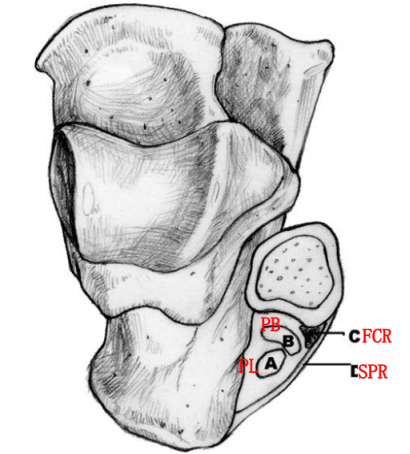

腓骨外踝窝:外踝的后方近端较宽广,远端呈锥形变小并有一浅的沟。

纤维软骨脊(FCR):腓骨外踝窝的外侧缘有一纤维软骨形成的缘,构成了窝的结构。该纤维软骨脊近端明显,向远端渐变小,使得沟的整体深度增加了2-4mm,且形状更适于容纳腓骨肌腱,从而促进应力分散。

腓骨上支持带(SPR):起于腓骨外侧面和腓骨外踝窝,绕过腓骨肌腱后止于跟骨和跟腱外侧。SPR没有直接牢固固定于纤维软骨脊,而是与腓骨外侧面的骨膜融合。

I型:最常见(51%),腓骨上支持带(SPR)和骨膜仍保持联系,骨膜从外踝上撕脱,腓骨肌腱滑向前方使骨膜和外踝分离。

Ⅱ型:(33%)纤维软骨脊连同腓骨上支持带(SPR)一起和外踝分离,腓骨肌腱向前脱位。

Ⅲ型:(16%)纤维软骨脊连同部分外踝骨质和腓骨上支持带(SPR)一起与外踝分离,肌腱脱位至骨折块下方。

IV型:Oden1987年在此基础上外,还有少见的第IV型,表现为腓骨上支持带(SPR)的完全撕脱或断裂,并且肌腱移位于支持带的外表面。